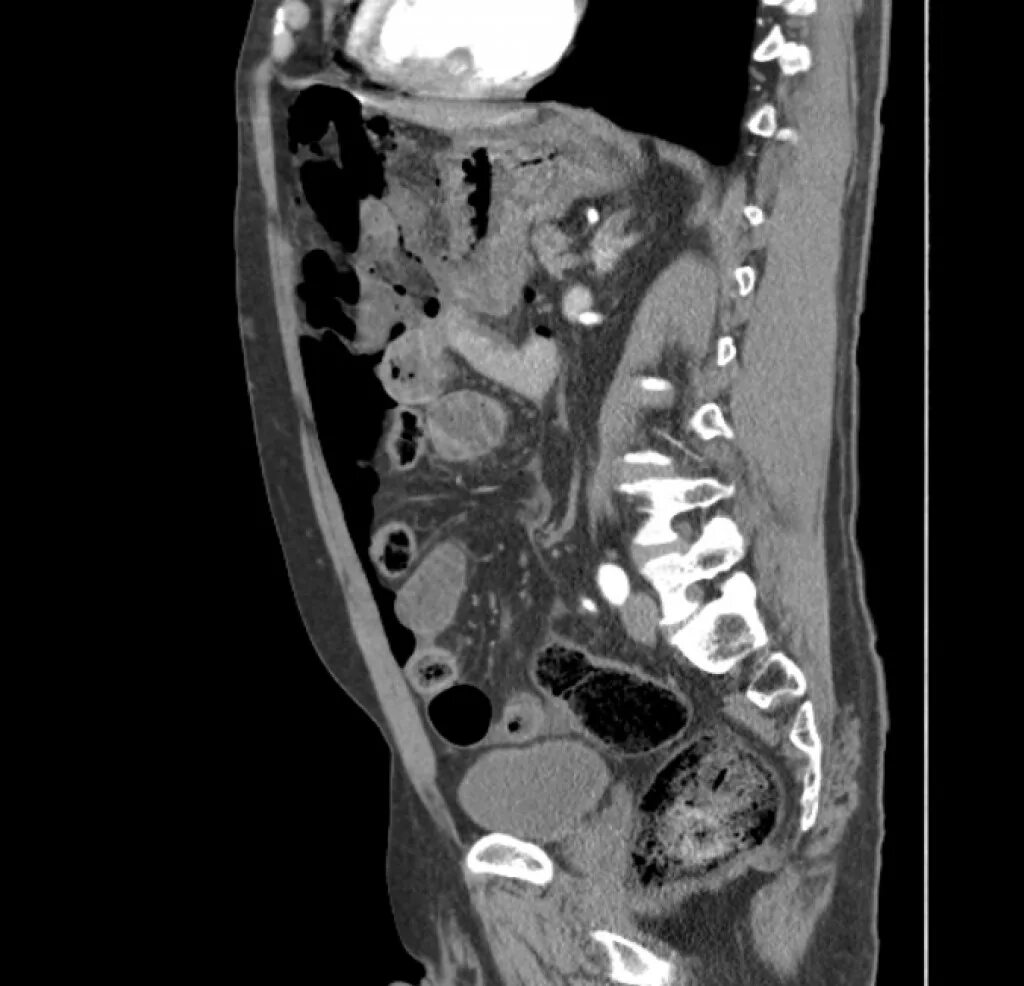

Язва желудка кт